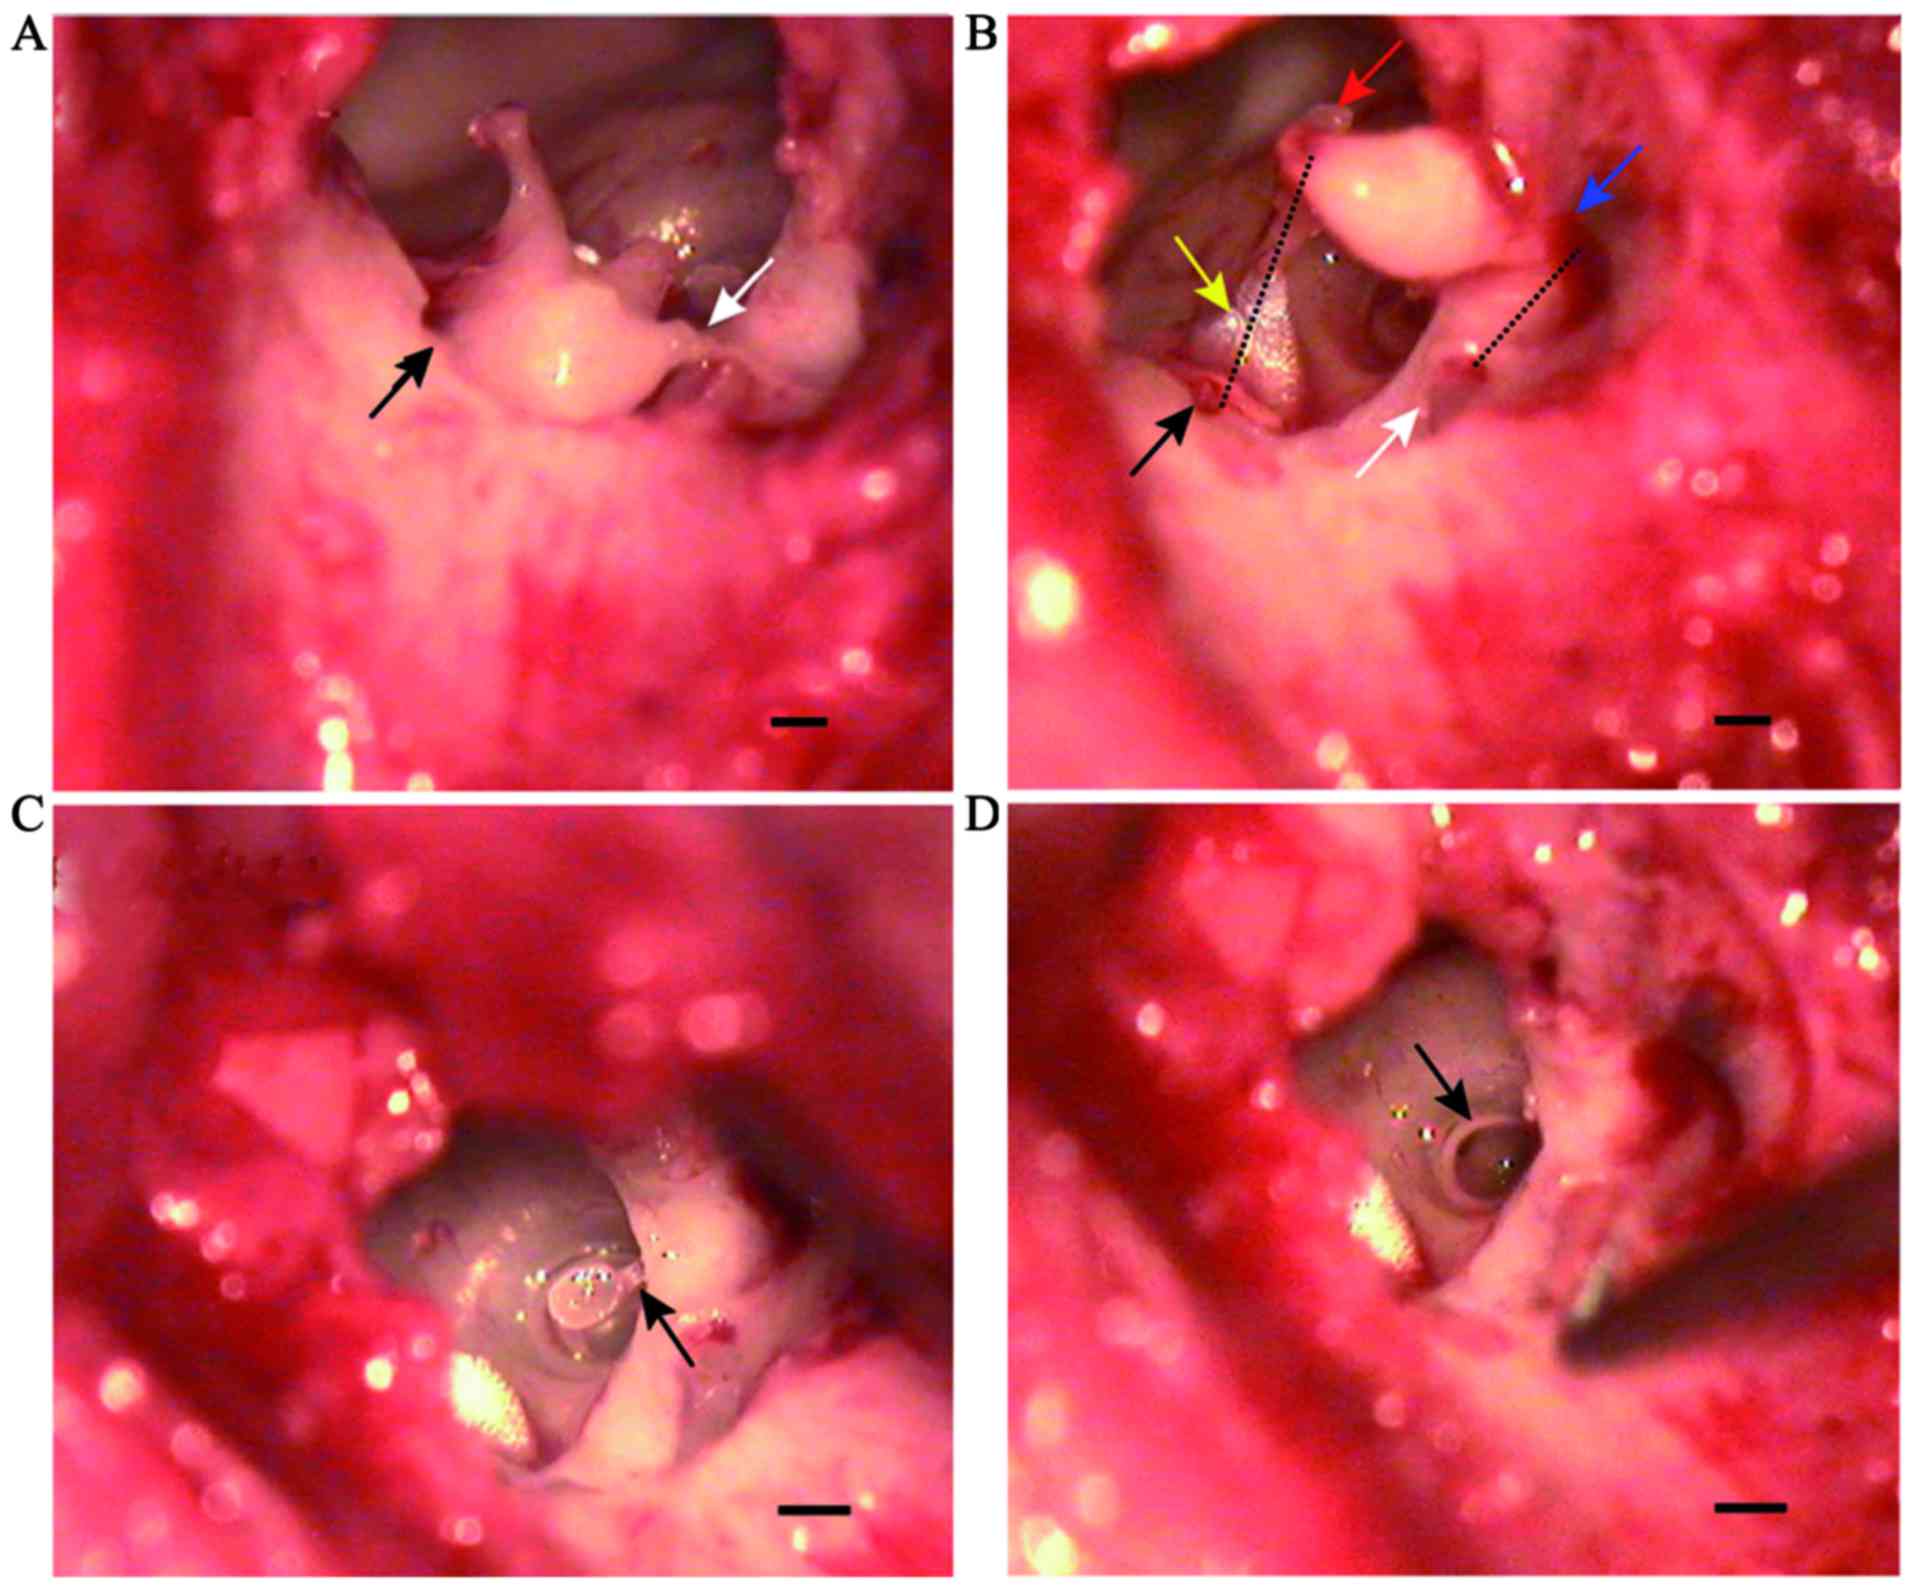

Ossicular ligament and ossicular muscle in the middle ear

After separating the incudostapedial joint and moving the auditory ossicular chain, the ligaments and muscles connecting the auditory ossicles could be observed, including the anterior ligament of malleus, posterior ligament of incus, annular ligament of stapes, tensor tympani and stapedius. The anterior ligament of malleus connected the end of the anterior process of the malleus to the superior wall of the tympanic cavity. Furthermore, the posterior ligament of the incus connected the end of the short process of the incus to the posterior wall of the incudal fossa located in close proximity to the facial nerve (Fig. 4A and B). Tensor tympani arose from the medial wall of the tympanic cavity located superior to the tympanic ostium of the eustachian tube and ended at the distal handle of the malleus (Fig. 4B). Stapedius arose from the posterior wall of the tympanic cavity and ended in the posterior region of the stapes neck (Fig. 4C). The annular ligament of stapes was located around the footplate and connected to the vestibular window (Fig. 4D).

Figure 4.

Ossicular ligaments and muscles in the rabbit middle ear. (A) The anterior ligament of the malleus (black arrow) and the posterior ligament of the incus (white arrow) were observed. (B) The anterior ligament of the malleus connected the anterior process of the malleus (red arrow) to the superior wall of the tympanic cavity (black arrow). The posterior ligament of the incus connected the short process of the incus (blue arrow) to the incudal fossa (white arrow) in close proximity to the facial nerve. Tensor tympani (yellow arrow) began at the medial wall of the tympanic cavity, and ended at the distal handle of the malleus. (C) The stapedius (black arrow) began at the posterior wall of the tympanic cavity, and ended in the posterior region of the neck of staples. (D) The annular ligament of the stapes (black arrow) was located around the vestibular window. Scale bar=0.50 mm.